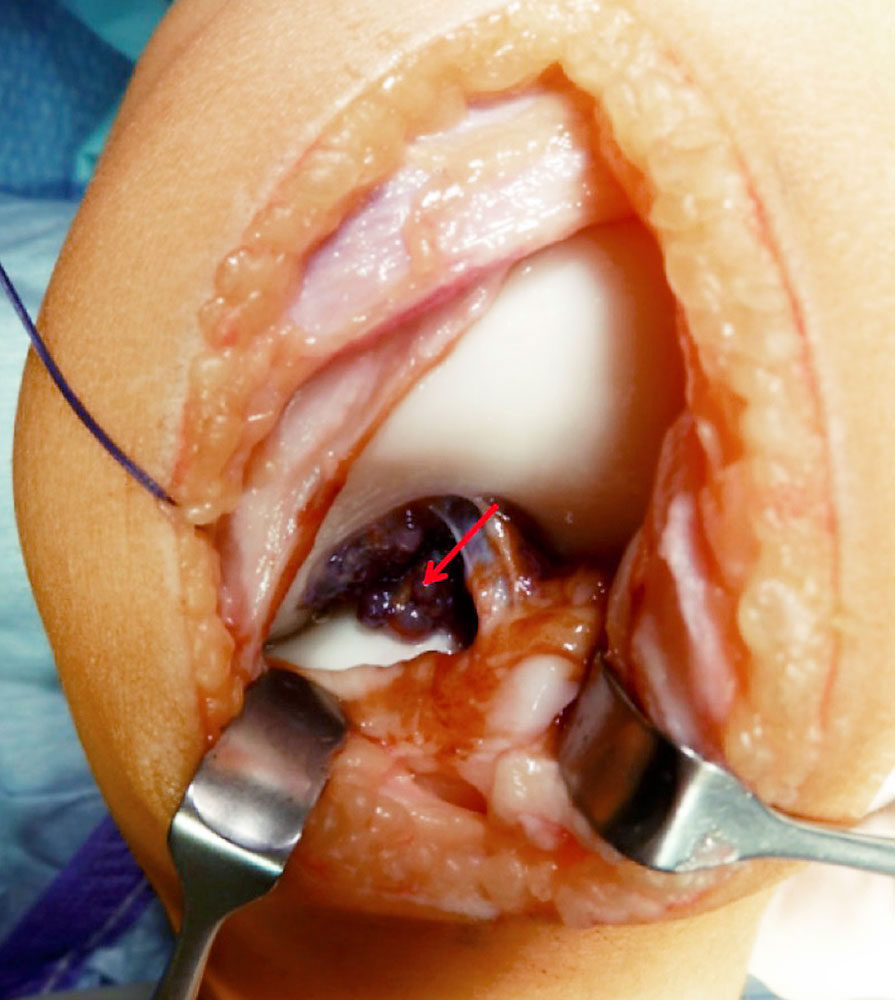

MRI then plays an essential role as a further diagnostic tool, as it can be used to assess a possible intra-articular extension of the malformation and to detect hemosiderin residues in the synovium in iron-sensitive sequences in a condition following direct bleeding in the joint.

Treatment should always be interdisciplinary. On the one hand, it requires interventional therapy of the peri-articular, or if possible intra-articular, vascular malformation to close vascular connections into the affected joint and to facilitate surgical access. On the other hand, it requires surgical removal of the peri- and intra-articular malformation and the altered synovium (synovectomy), if possible.

Surgical therapy can be either arthroscopic or open. Although the arthroscopic approach has clear advantages in terms of postoperative rehabilitation, it often cannot be used because of the extensive findings and more difficult bleeding control. Essentially, two factors play a role in why an open procedure must often be chosen:

• Large intra-articular vascular malformations with bleeding (even with a tourniquet in place) additionally worsen the arthroscopic overview.